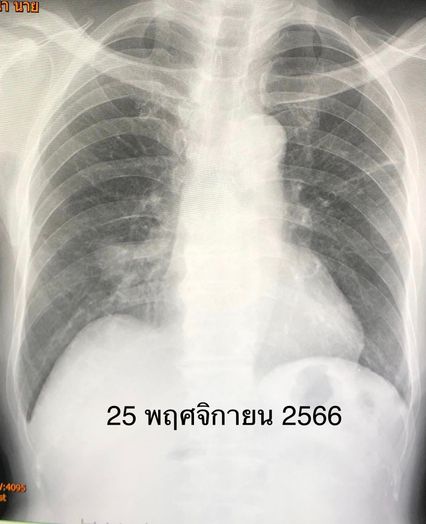

“ผลตรวจร่างกาย ฟังเสียงปอดพบความผิดปกติ เมื่อเอกซเรย์ปอดมีฝ้าขาวทั้งสองข้าง แพทย์จึงสั่งเก็บเสมหะส่งย้อมเชื้อพบวัณโรค 1+ ตรวจรหัสพันธุกรรมพบเชื้อวัณโรคไม่ดื้อยาริแฟมพิซิน เพาะเชื้อขึ้นวัณโรคไวต่อยาไอโซไนอะซิด ริแฟมพิซิน และอีแธมบูทอล สรุปว่า ผู้ป่วยเป็นวัณโรคปอดชนิดไม่ดื้อยา ได้เริ่มยาไอโซไนอะซิด ริแฟมพิซิน พัยราซินาไมด์ และอีแธมบูทอล หลังกินยาวัณโรค 2 สัปดาห์ ผู้ป่วยคลื่นไส้ อาเจียน เบื่ออาหาร ค่าเอนไชม์ตับขึ้นสูง SGOT 312, SGPT 199 แพทย์สงสัยว่าแพ้ยาริแฟมพิซินทำให้ตับอักเสบ จึงหยุดยาริแฟมพิซิน ให้ยามอกซิฟลอกซาซิน (Moxifloxacin) แทนยาริแฟมพิซิน ค่าเอนไชม์ตับลดลง SGOT 57, SGPT 36” หมอมนูญระบุ

เคสนี้แพทย์รักษาด้วยการให้กินยาวัณโรคไอโซไนอะซิด พัยราซินาไมด์ อีแธมบูทอล และมอกซิฟลอกซาซิน ต่อเนื่อง 1 ปี ไม่ไอ มีความอยากอาหาร น้ำหนักขึ้น 14 กิโลกรัม ผลเอกซเรย์ปอดดีขึ้นมาก หลังหยุดกินยา 4 ปี วัณโรคไม่กลับมาใหม่ เอกซเรย์ปอดยังมีร่องรอยวัณโรคเก่าบ้าง